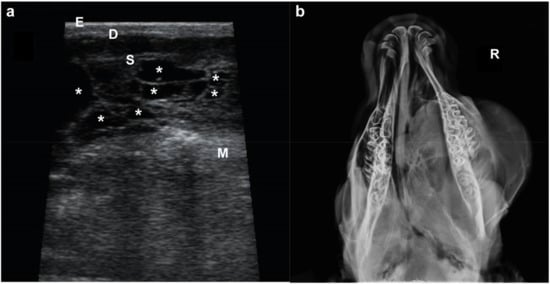

Ultrasound examination (US) of the infraorbital mass and radiography of the head were performed. At US the mass displayed an irregular shape with a multiple cavities (Figure 2a). Radiographs were performed to the skull in a dorsal-ventral view, and revealed a diffuse, poorly defined mass with different densities overlying the bony structures of the skull.

Figure 2. Imaging of the suborbital mass. (a) US image showing the three superficial layers (E, epidermis; D, dermis; S, subcutaneous tissue) overlying the malaris muscle (M) (note the bright hyperechoic appearance) and the mass with an irregular shape and multicavitary (*) (note the septated cavities filled with an anechogenic content) delimitated by S and M. (b) Radiography of the head in a dorso-ventral view (note that the mass extends to the left side of the hard palate). R, right side.